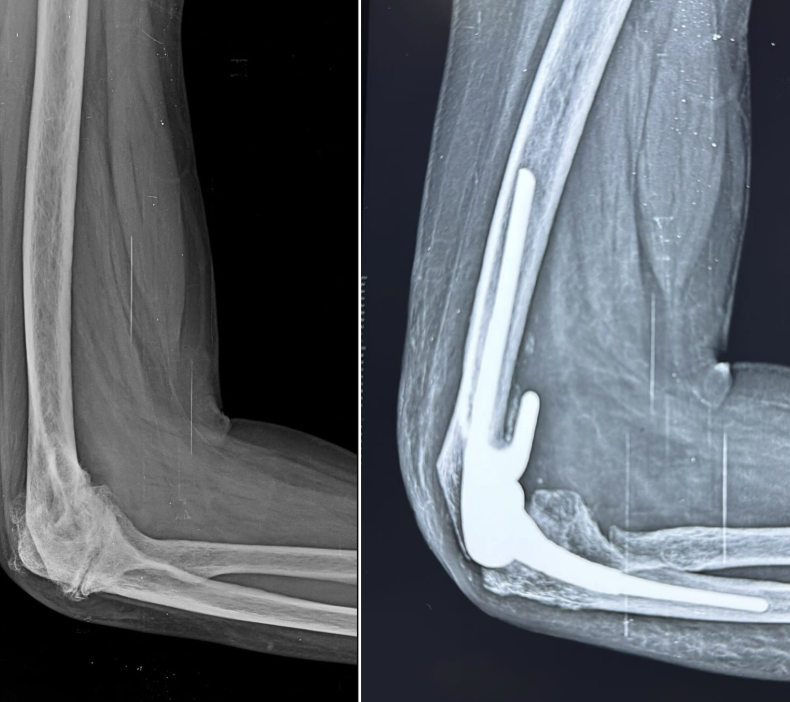

Total Elbow Replacement (Arthroplasty)

Total elbow replacement (TER) — or total elbow arthroplasty (TEA) — replaces the diseased articular surfaces of the distal humerus and proximal ulna (and radial head when required) with a linked or unlinked prosthetic implant. It is less commonly performed than hip or knee replacement but is a highly effective procedure for appropriately selected patients with end-stage elbow arthritis or complex fractures.

Linked (Semi-Constrained) | The humeral and ulnar components are connected by a pin mechanism with intentional laxity. The most commonly used type. Not reliant on collateral ligament integrity. The Coonrad-Morrey prosthesis is the gold standard linked implant with >20-year follow-up data. |

Total elbow replacement is performed under general anaesthesia with a tourniquet. A posterior midline incision provides exposure. The triceps mechanism is reflected (or split) to expose the joint; the diseased articular surfaces are resected with precision cuts; and the implants are secured with bone cement. The triceps is meticulously repaired and the wound closed.